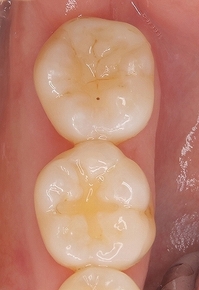

術後1年1ヵ月 口腔内

2026 EEdental TAY (4).jpg

*一番上の歯を治療させてもらいました。

問題無く経過しており、綺麗に残せて良かったです!